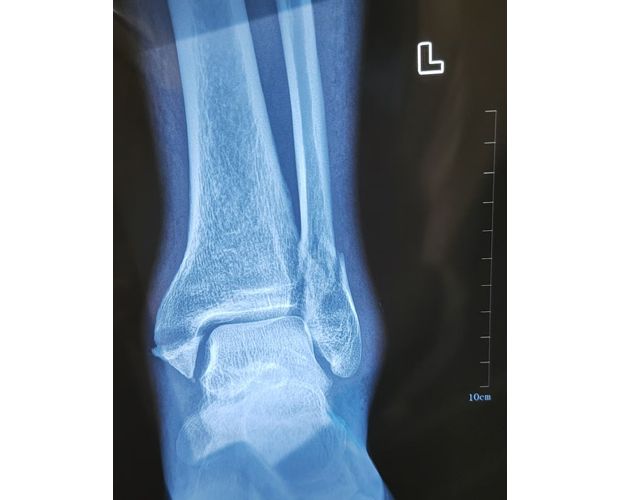

2月4日,何店镇中心卫生院接诊一名左踝关节外伤患者,经影像检查,确诊为左胫、腓骨下段骨折。外科医生姜稳迅速完成术前检查及病情评估,并与患者及家属深入沟通治疗方案。在患者强烈要求于本院进行手术的情况下,为最大限度保障手术质量与安全,该院特邀请医共体牵头单位——曾都区人民医院脊柱创伤外科专家团队前来指导。